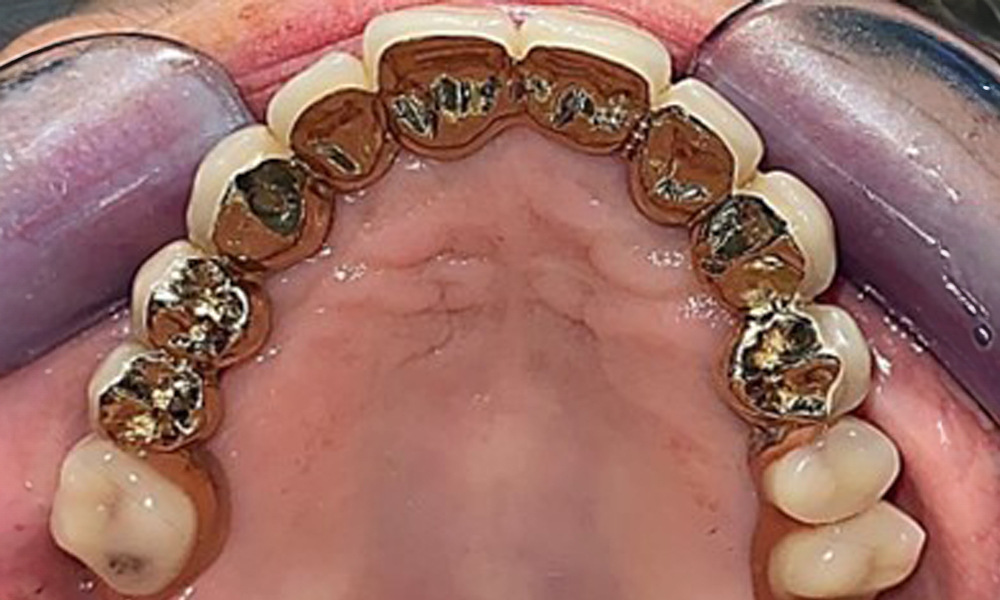

Occlusal view: Maxilla with tooth and implant-supported telescopic prostheses.

Fig. 2: Occlusal view: Maxilla with tooth and implant-supported telescopic prostheses

The dental findings are as follows: Combined removable implant and tooth-supported telescopic prostheses on implants 15, 13, 21, 23, 24, 25 and tooth 11 (Fig. 1, Fig. 2, Fig. 3). The patient was fitted with a fixed mandibular denture. Adequate bridges were present over 37 to 34 and 45 to 47 (Fig. 4), the crown margins were intact and there were no active caries. A composite filling with a marginal gap was present on tooth 43. There was mandibular gingival recession, exposing 1 to 3 mm of root surface. This also applies to 11.